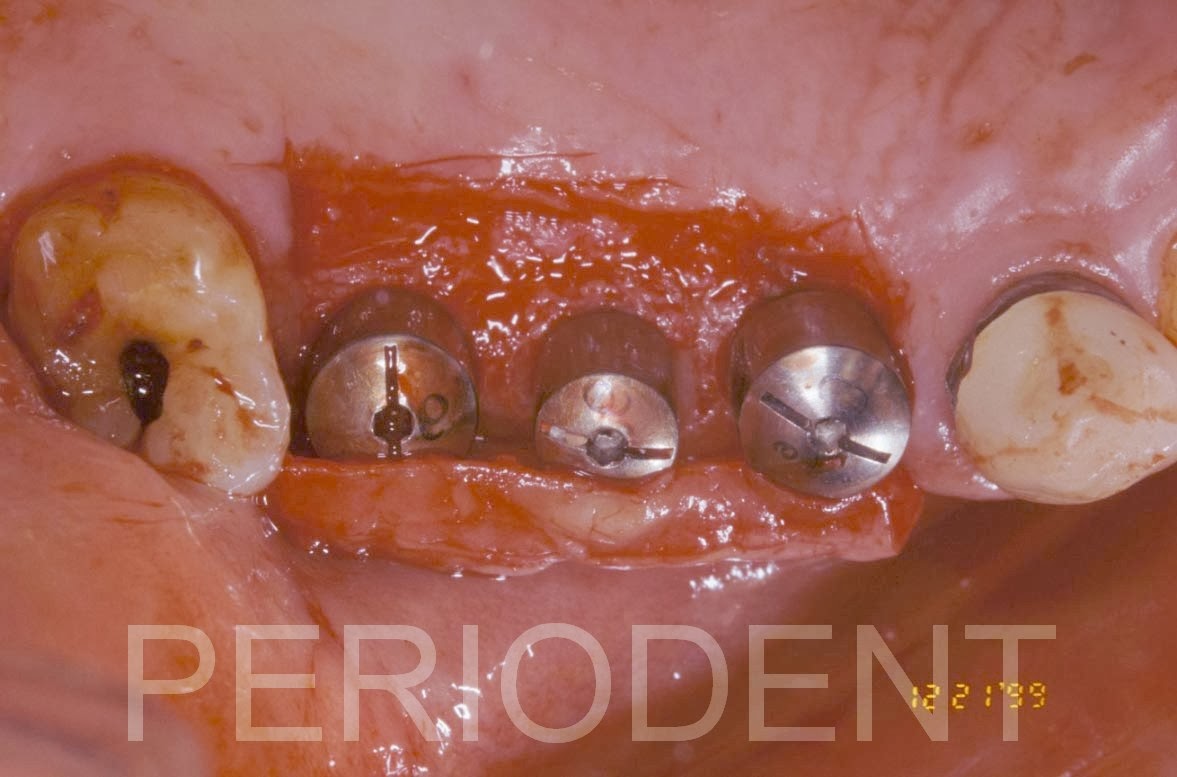

植牙第二階段時採用Rolled方式

癒合後